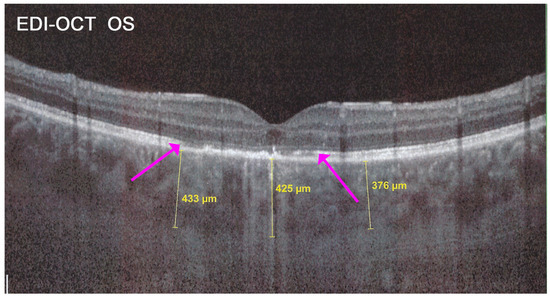

Figure 25. APMPPE/AMIC; EDI-OCT (same case as Figure 21 and Figure 22). Besides the loss of photoreceptor outer segments (marked by crimson arrows), the whole choroid is thickened, with callipers showing values between 376 µm and 433 µm.

The exact extensions of bilateral lesions were clearly delineated on ICGA showing scattered small hypofluorescent areas of choriocapillaris non-perfusion OD and more confluent hypofluorescent lesions OS (Figure 24), corresponding to areas of hyperautofluorescence on BL-FAF and FA hyperfluorescence (Figure 24). SD-OCT showed loss of photoreceptor outer segments and irregularity of the IS/OS line due to ischaemia following choriocapillaris non-perfusion (Figure 24). FA hyperfluorescence is explained by compensatory retinal exudation with limited pooling as the patient was already under corticosteroid therapy. Besides choriocapillaris non-perfusion, the whole choroidal thickness was increased (Figure 25).

In addition to choriocapillaris non-perfusion, in most acute cases, the entire choroid is thickened, which can be shown by enhanced depth imaging OCT (EDI-OCT) (Figure 11). In complement to ICGA, OCT angiography (OCT-A) shows areas of choriocapillary drop-out that correlate with the areas of ICGA hypofluorescence the analysed area being however, limited to part of the posterior pole and less precise than ICGA [5,7,25] (Figure 12).